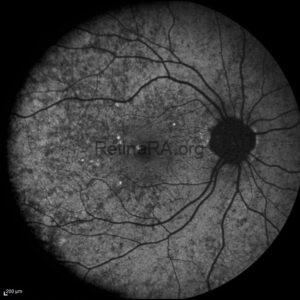

Retinitis Pigmentosa

A 42-year-old male presented with progressive night blindness and peripheral visual field constriction, accompanied by [...]